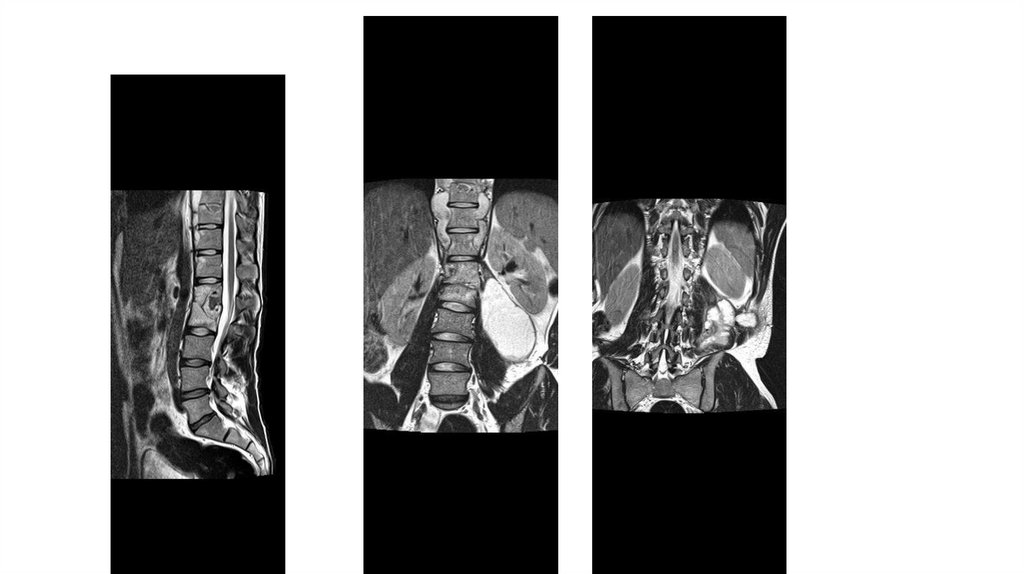

Воспалительные заболевания опорнодвигательного аппарата

заболевания опорнодвигательного аппарата»